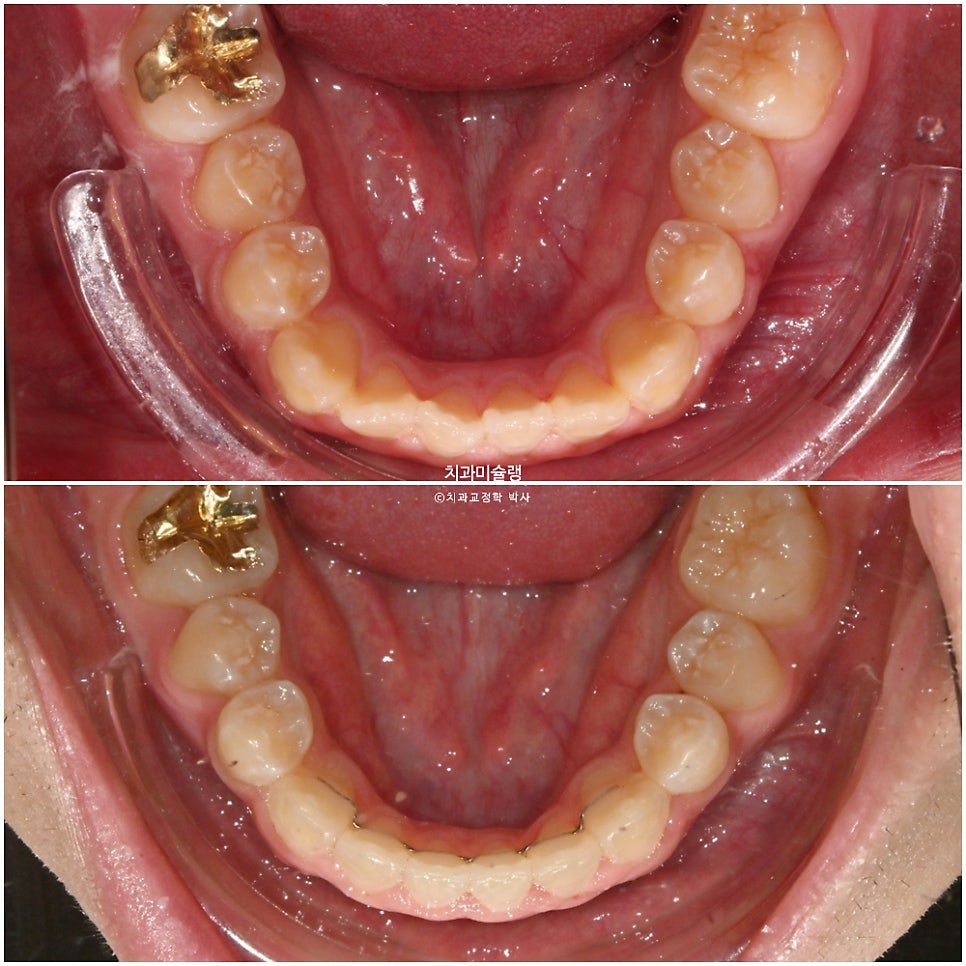

좌측 소구치 하나가 입천장으로 들어가 있는데 180도 회전된 상태입니다.

180도 돌아가 있던 소구치는 굳이 180도 돌려 원위치 시키지 않습니다.

약 90도 정도 돌아가 있다면야 원위치 시킬만 하지만, 아예 180도 거꾸로 난 상태에서는 그대로 배열해도 교합상 문제가 되지 않기 때문이죠. 잇몸과 치근흡수 부담을 줄이는 장점도 있습니다.